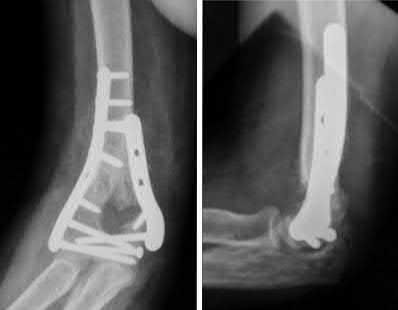

Figures A and B demonstrate a distal third tibial shaft fracture with simple intra-articular extension. The axial and coronal CT cuts in Figures C and D further clarify the articular injury. Illustrations A and B demonstrate a comminuted distal third tibial fracture with simple intra-articular extension. Illustrations C and D are fluoroscopic images of the same injury after intramedullary nailing and percutaneous fixation of the articular component.